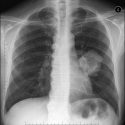

El anticuerpo monoclonal Pembrolizumab es eficaz en el tratamiento de primera línea de pacientes con cáncer de pulmón no microcítico (CPNM) metastásico, según los resultados de dos estudios presentados en el Congreso anual de la Sociedad Europea de Oncología Médica (ESMO). El tratamiento con esta “bala mágica” puede producir una mejora significativa con respecto a la quimioterapia en una amplia gama de pacientes.

En este sentido, estos estudios pueden representar un punto de inflexión en los esfuerzos internacionales para controlar el cáncer de pulmón. En concreto, en el estudio ‘Keynote-024’, cuyos datos han sido publicados en The New England Journal of Medicine y en el que se evaluó a pacientes con CPNM escamoso y no escamoso cuyos tumores expresaban niveles elevados de PD-L1, este fármaco de MSD produjo una reducción del 50 por ciento del riesgo de progresión de la enfermedad o de muerte y una reducción del 40 por ciento del riesgo de muerte en comparación con el doblete de quimioterapia con platino, el tratamiento de referencia actual.

Se trata del único tratamiento anti-PD-1 que hasta la fecha ha conseguido demostrar una supervivencia libre de progresión (SLP) y una supervivencia global (SG) mejores que la quimioterapia como tratamiento de primera línea del CPNM escamoso y no escamoso en pacientes con tumores que expresan niveles elevados de PD-L1 y que no tienen alteraciones genéticas en el EGFR o en el ALK.